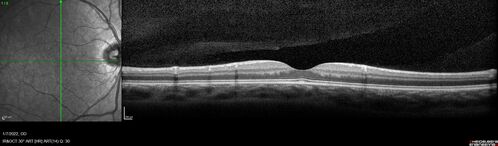

Combined hamartoma of the retina and retinal pigment epithelium

8 year old boy failed vision screening at school. VA 20/20 OD, 20/40 OS

Combined hamartoma of the retina and the retinal pigment epithelium